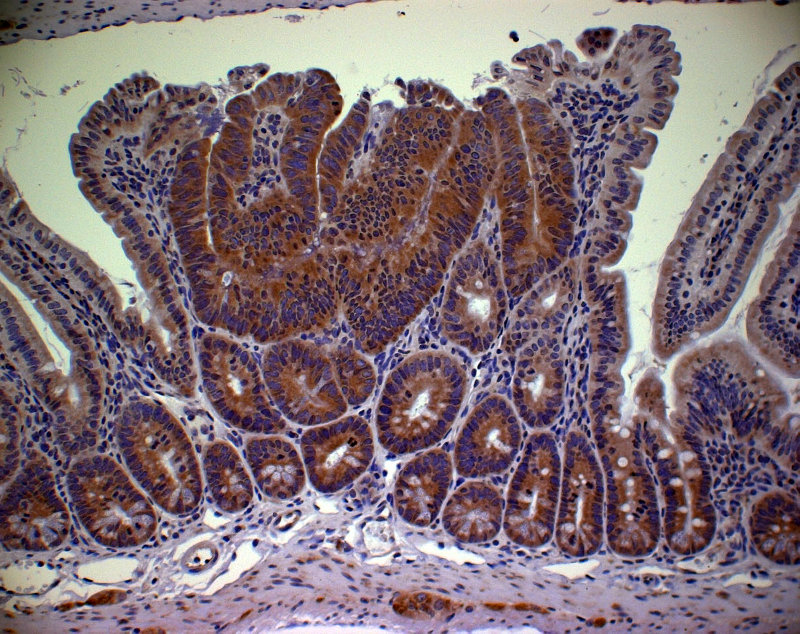

A study published today used the Sleeping Beauty transposon system to profile the repertoire of genes that can drive colorectal cancer, identifying many more than previously thought. Around one third of these genes are mutated in human cancer, which provides strong evidence that they are driver mutations in human tumours.

The Sleeping Beauty transposon system induces genetic mutations at random, identifying and tagging candidate cancer genes, the drivers that cause colorectal cancer. This system has become critical in uncovering the genetic pathways that cause cancer, and, in this study, the team identify more than 200 genes that can be disrupted in human colorectal cancers.

Colorectal (bowel) cancer is the third most common cancer in the UK, and the second most common cause of cancer deaths after lung cancer; just under 40,000 people were diagnosed with bowel cancer in the UK in 2008 – around 110 people every day – a figure which has shown little improvement over the last decade.